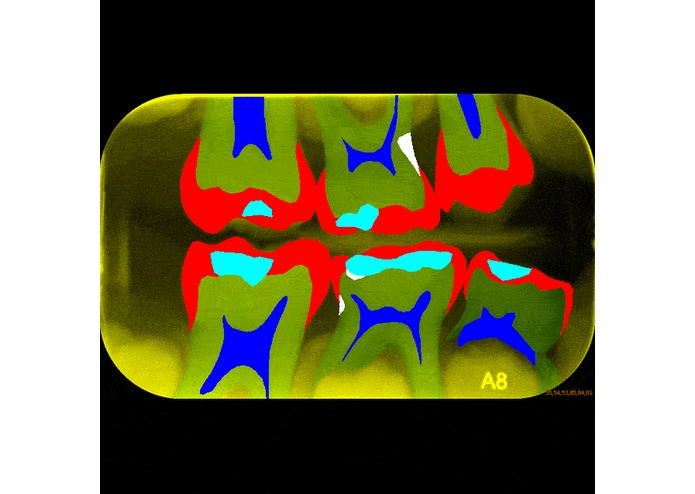

Our website demonstrates promising results of deep image segmentation applied to x-ray images of teeth. We show the separation of different classes using color coded labels and describe useful use-cases of further work in this direction.

During this weekend, our time was mostly spent on implementation of the U-Net model. The author achieved very good results for Biomedical image segmentation with a limited amount of training samples. We used a small open-source dataset of dental x-ray images. In addition to this, we spent some time to solidify the use-cases for this model, as well as related additional work.